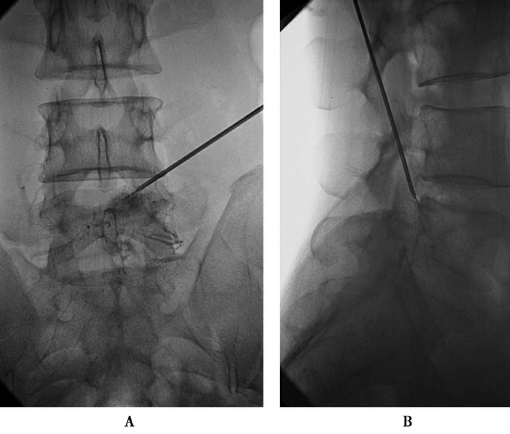

上关节突尖的稍背侧(图11):0.5%利多卡因局麻后用勺状针由穿刺点与额状面呈20°缓缓进针,边进针边注入局麻药,达上关节突尖的稍背侧,抵骨,注入局麻药10ml。

图11 勺状针针尖抵达上关节突尖的稍背侧A.前后位透视;B.侧位透视